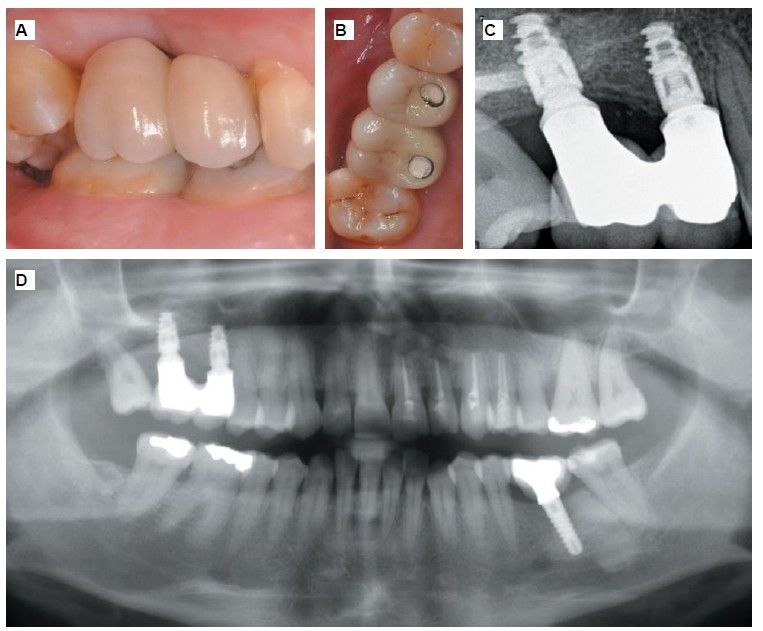

Six months after the maxillary sinus elevation surgery, re-entry was performed for the placement of implants. A 3 x 7mm bone tissue biopsy was obtained using a trephine, and histomorphometric analysis was requested, revealing 30.56% vital bone (Figure 7). After the biopsy sample was taken, two bone level Naturactis implants from ETK® (ETK Implants S.L, Sant Boi de Llobregat, Spain) were placed with an insertion torque of 35 Ncm, and their correct positioning was confirmed in the immediate postoperative period by means of a periapical radiograph (Figure 8). Six months after the placement of the implants, the patient was able to attend for the second stage to place healing abutments. A verification CBCT was performed to assess the final bone height, revealing an increase of 4.2 mm in the region of 1.6 and 6.1 mm in the region of 1.7 (Figure 9).

Fifteen days after the second stage, impressions were taken for the fabrication of two splinted cement-screw-retained crowns on titanium bases, with the fit verified by a parallelised periapical radiograph (Figure 10). Six months after placement of the restoration, a clinical and radiographic review was conducted, noting the favourable condition of the soft tissues (Figure 11).